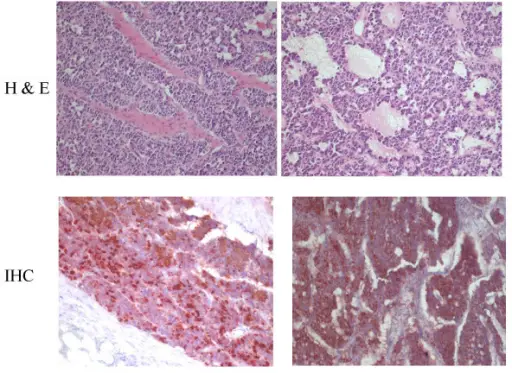

Pheochromocytoma

A particular kind of neuroendocrine tumor (NET) known as a pheochromocytoma develops from chromaffin cells.

Chromaffin cells are located in the adrenal glands and create hormones that the body requires.

Clinical features of pheochromocytoma results from elevated serum catecholamine levels.

Clinical features of pheochromocytoma include:

- Perspiration

- Tachycardia

- Palpitations

- Headaches

- Episodic hypertension

Increased 24-hour urine production and serum metanephrine levels are used to diagnose the disease.

Medical excision is used as a treatment of choice.

When the tumor is manipulated, catecholamines may leak into the bloodstream.

An irreversible alpha-blocker called phenylbenzylamine is given preoperatively to stop a hypertensive crisis.

Pheochromcytomas often follows the rule of 10s:

- 10% bilateral

- 10% familial

- 10% malignant

- 10% located outside of the adrenal medulla such as bladder wall or organ of Zuckerkandl at the inferior mesenteric artery root